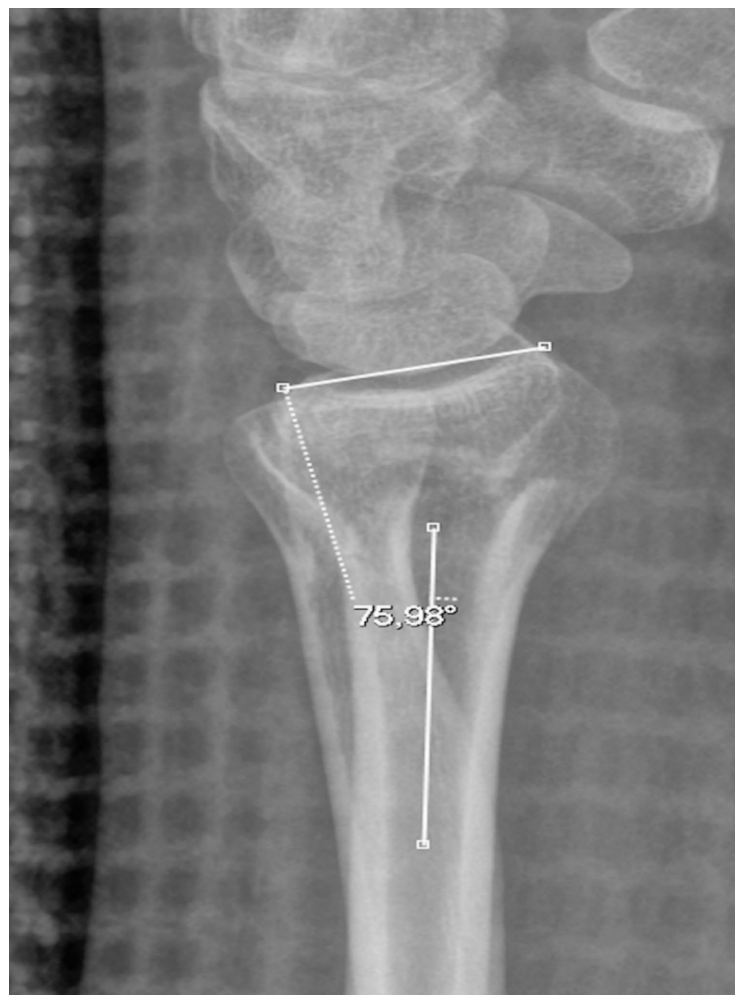

丹麦欧登塞大学医院(Odense University Hospital)和南丹麦大学(University of Southern Denmark)的Sebastian P.L. Clark团队在《Emergency Radiology》发表的这项研究,通过一个戏剧性的临床案例揭开了这个测量谜团。一位35岁男性运动员在就诊时,间隔仅1分钟拍摄的两张侧位X线片显示出截然不同的背侧倾斜角度(2.5° vs 14°)。这种"魔术般"的变化最终被证实源于前臂的旋后体位——当采用Scaphopisocapitate(SPC)对齐标准重新评估时,旋后体位导致的测量误差昭然若揭。

研究人员采用了两项关键技术:首先是Yang等提出的SPC对齐标准,通过观察豌豆骨(pisiform)与舟骨(scaphoid)、头状骨(capitate)的解剖关系判断真侧位影像;其次是Kreder等建立的背侧倾斜角度测量方法,即桡骨远端关节面背侧与掌侧边缘连线与桡骨纵轴的夹角。这些方法在骨折标本和临床病例中经过放射立体测量分析(Radiostereometric Analysis, RSA)验证。